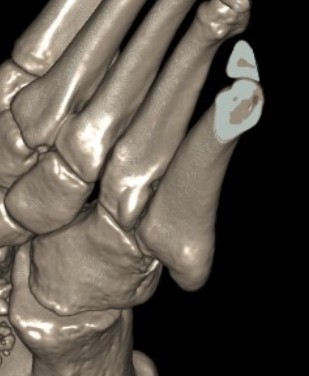

Imaging

1. Diastasis of the intermetatarsal gap between the 1st and 2nd metatarsals

2. Widening of the space between the medial cuneiform and base of 2nd metatarsal

3. Second metatarsal Fleck sign - avulsion of Lisfranc ligament from base of 2nd metatarsal

4. Widening of inter-cuneiform distance

5. Dorsal subluxation of the metatarsals

6. Tarsometatarsal alignment disruption

- medial border 1st metatarsal aligns with medial border medial cuneirform (AP foot)

- medial border 2nd metatarsal aligns with medial border middle cuneiform (AP foot)

- medial border 3rd metatarsal aligns with medial border lateral cuneiform (AP view)

- medial border 4th metatarsal aligns with medial border of the cuboid (oblique view)

CT scan

Dorsal displacement of metatarsals

Compression fractures / nutcracker of cuboid